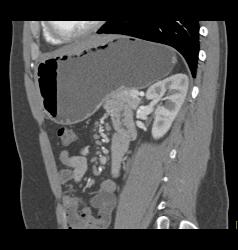

Antral Carcinoma